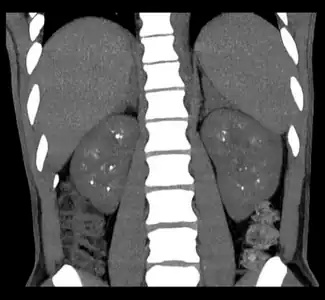

Non-contrast coronal CT depicts nephrocalcinosis.

Nephrocalcinosis is diagnosed for the most part by imaging techniques. The imagings used are ultrasound (US), abdominal plain film and CT imaging.[11] Of the 3 techniques CT and US are the more preferred. Nephrocalcinosis is considered present if at least two radiologists make the diagnosis on US and/or CT. In some cases a renal biopsy is done instead if imaging is not enough to confirm nephrocalcinosis. Once the diagnosis is confirmed additional testing is needed to find the underlying cause because the underlying condition may require treatment for reasons independent of nephrocalcinosis.[11] These additional tests will measure serum, electrolytes, calcium, and phosphate, and the urine pH.[11] If no underlying cause can be found then urine collection should be done for 24 hours and measurements of the excretion of calcium, phosphate, oxalate, citrate, and creatinine are looked at.[11]